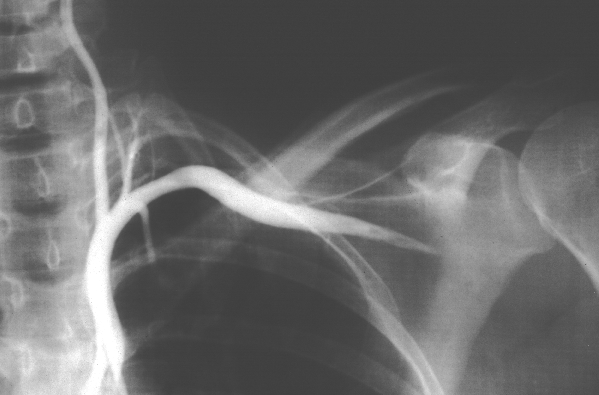

Upper Limbs: Shoulder and Neck Angiogram